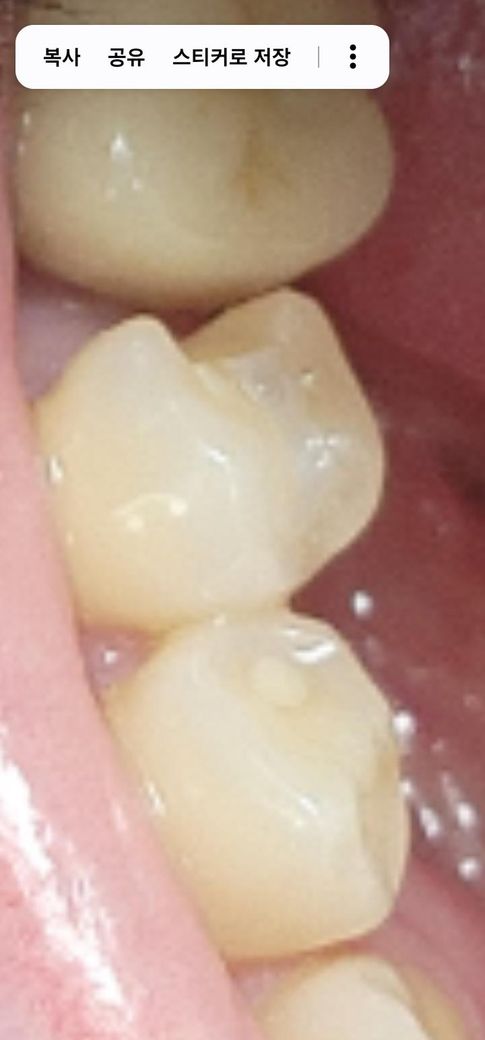

어제 혀로 치아를 건들다가 파인 느낌이 나서 보니 치아가 깨진게 보이더라구요

치아 또는 기존에 떼웠던 수복물, 보철물이 탈락, 파절된 것 같습니다. 그냥 두면 치아가 더 깨져나가거나, 음식물이 잘 껴서 충치가 생길 수 있으니 처치를 받으시면 좋을 것 같습니다.

예전에 인레이나 레진으로 수복해놓았는 부분이 깨져나간 것으로 보입니다. 그대로 둘 경우에는 음식물이 끼이고 충치나 염증이 발생할 수 있으므로 치과에가서 치료 받으시길 바라겠습니다.

치아의 인접면이 파절된 것으로 보입니다. 치아에 인접면이 파절되면 해당 부위에서 이제 음식물이 끼게 되고 충치나 치주 질환을 유발할 수 있습니다. 인레이나 크라운보 철을 해주는 것이 좋습니다.